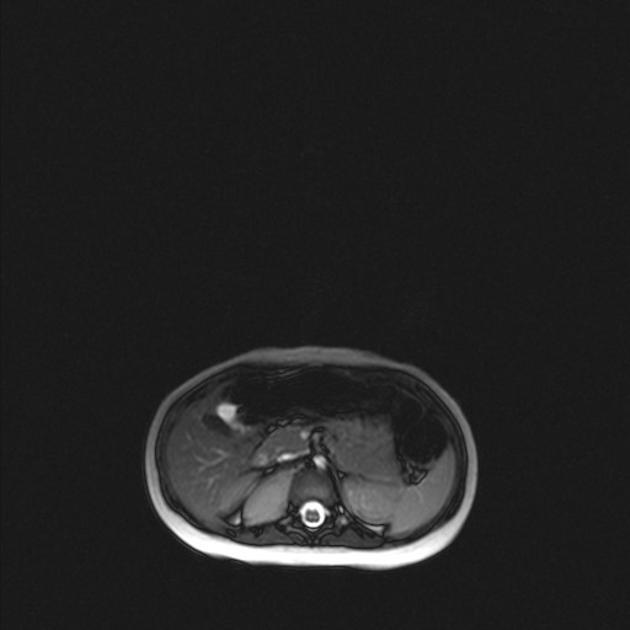

Main differences between Wilms and Neuroblastoma

Calcifications and metastasis to bones in neuroblastoma

Invasion of vessels and well defined in Wilms (neuro encases and is irreguar)

4 years in Wilms and 2 years in Neuro